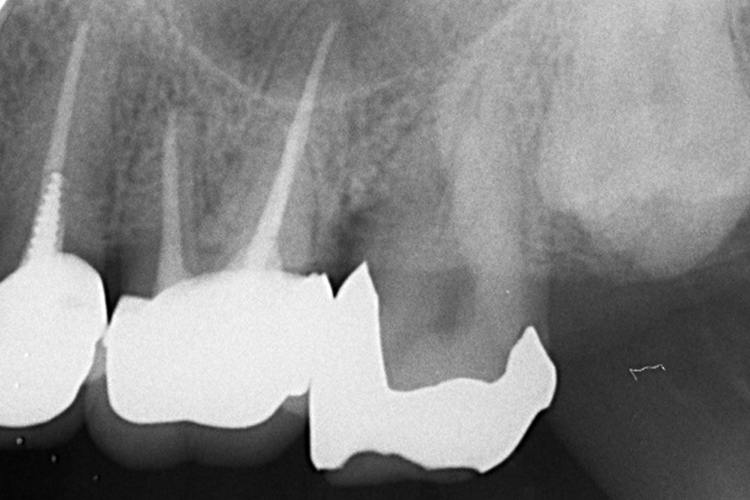

施術前のレントゲンと口腔内写真です。施術前にプラークの除去を行ってから、施術します。

施術前のレントゲンと口腔内写真です。